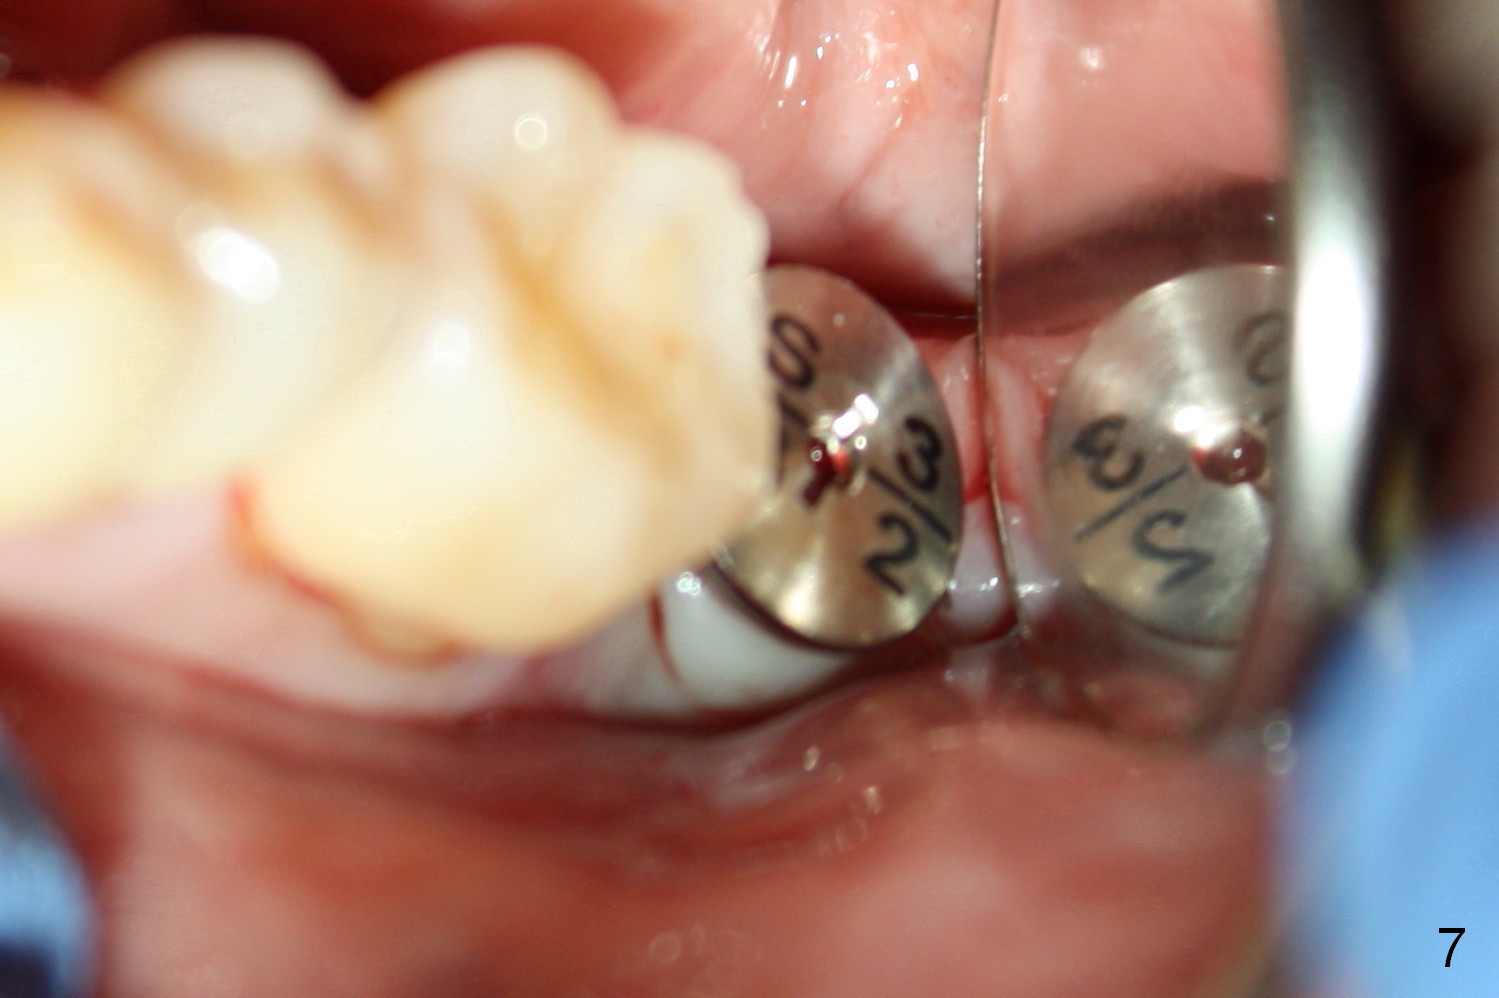

A 48-year-old lady is a dental phobic, requesting extraction of the lower left 2nd molar (Fig.1).   She returns for implant placement 9 months post extraction (Fig.2).  The ridge is mildly to moderately atrophic.  It appears that a 5x12 mm implant is appropriate for the site (Fig.3).  For safety, osteotomy is initiated at the depth of 10 mm; it appears that there is enough height for a 12 mm implant (Fig.4).  The depth is controlled by drill stopper (Fig.5 S).  Finally a 5x12 mm implant is apparently safely placed (Fig.6).  A healing abutment is placed and the incision is sutured with 4-0 Chromic gut (Fig.7).  Perio dressing is applied around the healing abutment for wound protection (Fig.8).  It appears that the healing abutment (Fig.8': *) helps stabilize the perio dressing, which remains in place 1 week postop.  When the perio dressing is removed, the wound around the healing abutment is healing (Fig.9).  There is no bone loss around the implant 3 months postop (Fig.10 (H: healing abutment), or 16 months postop (i.e., 9 months post cementation, Fig.11,12).  The patient complains of pain when she chews with the implant crown, but pain stops whenever she does not bite.  Percussion does not elicit any discomfort.  The gingiva is healthy.  There is possibility of the buccal plate being thin or the lingual plate being perforated in the submandibular fossa.  If the discomfort remains the same next 6 months, CBCT will be prescribed.